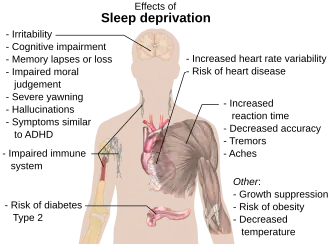

Generally speaking, the longer an organism is awake, the more it feels a need to sleep ("sleep debt"). This driver of sleep is referred to as Process S. The balance between sleeping and waking is regulated by a process called homeostasis. Induced or perceived lack of sleep is called sleep deprivation.

Sleep deprivation tends to cause slower brain waves in the frontal cortex, shortened attention span, higher anxiety, impaired memory, and a grouchy mood. Conversely, a well-rested organism tends to have improved memory and mood.[39] Neurophysiological and functional imaging studies have demonstrated that frontal regions of the brain are particularly responsive to homeostatic sleep pressure.[40]

Low quality sleep has been linked with health conditions like cardiovascular disease, obesity, and mental illness. While poor sleep is common among those with cardiovascular disease, some research indicates that poor sleep can be a contributing cause. Short sleep duration of less than seven hours is correlated with coronary heart disease and increased risk of death from coronary heart disease. Sleep duration greater than nine hours is also correlated with coronary heart disease, as well as stroke and cardiovascular events.[125][126][127][128]

In both children and adults, short sleep duration is associated with an increased risk of obesity, with various studies reporting an increased risk of 45–55%. Other aspects of sleep health have been associated with obesity, including daytime napping, sleep timing, the variability of sleep timing, and low sleep efficiency. However, sleep duration is the most-studied for its impact on obesity.[125]

Sleep problems have been frequently viewed as a symptom of mental illness rather than a causative factor. However, a growing body of evidence suggests that they are both a cause and a symptom of mental illness. Insomnia is a significant predictor of major depressive disorder; a meta-analysis of 170,000 people showed that insomnia at the beginning of a study period indicated a more than the twofold increased risk for major depressive disorder. Some studies have also indicated correlation between insomnia and anxiety, post-traumatic stress disorder, and suicide. Sleep disorders can increase the risk of psychosis and worsen the severity of psychotic episodes.[125]